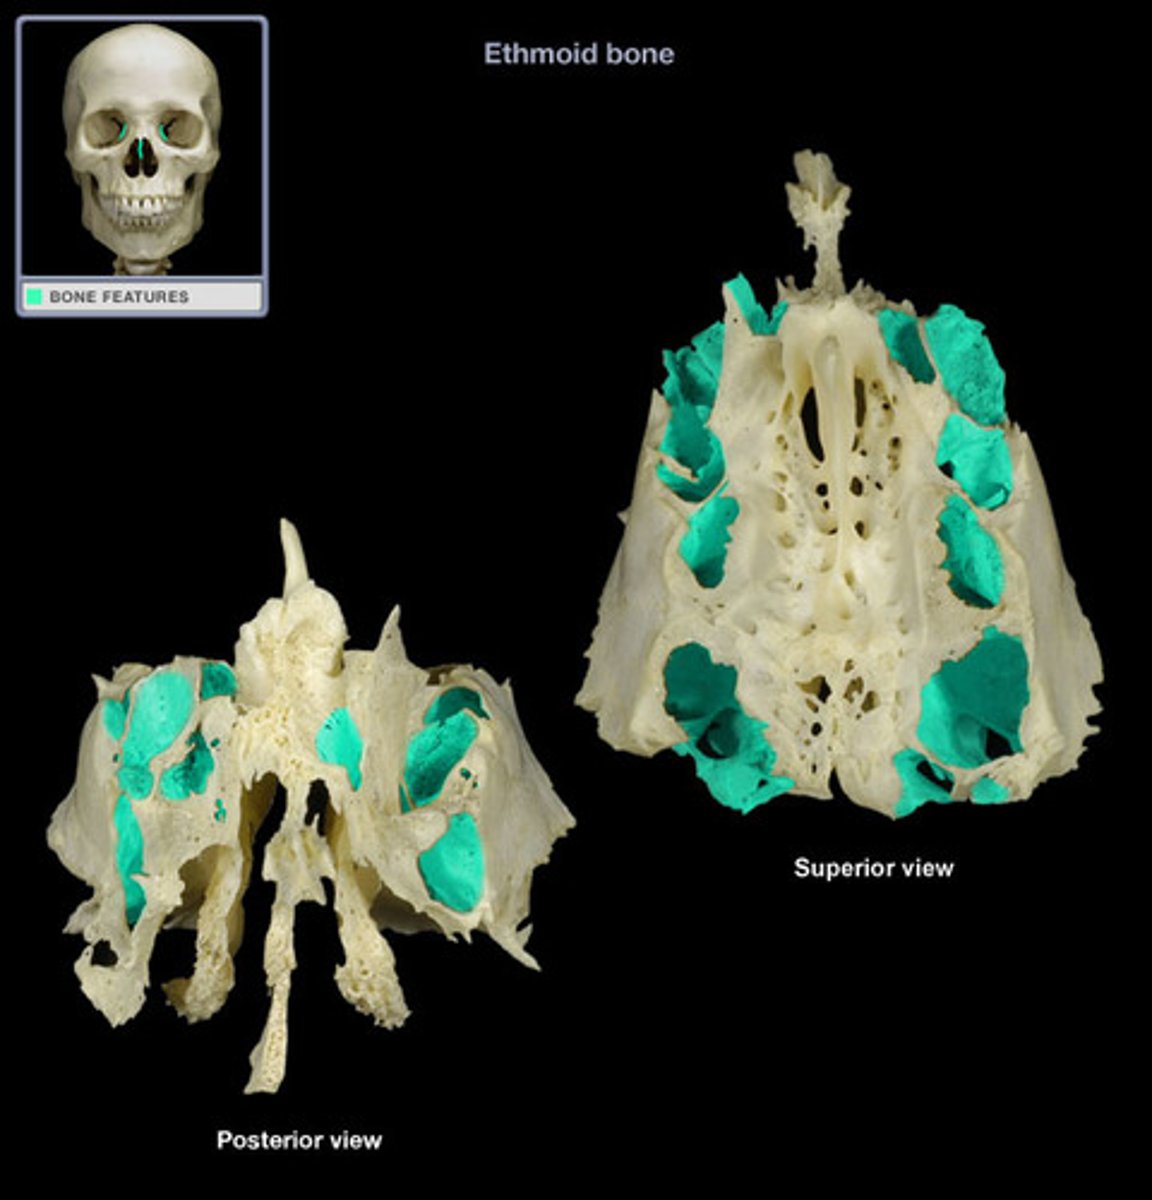

Ethmoid bone

ethmoidal notch

orbital plate

cribriform plate

crista galli

perpendicular plate

labyrinths

superior & middle nasal conchae